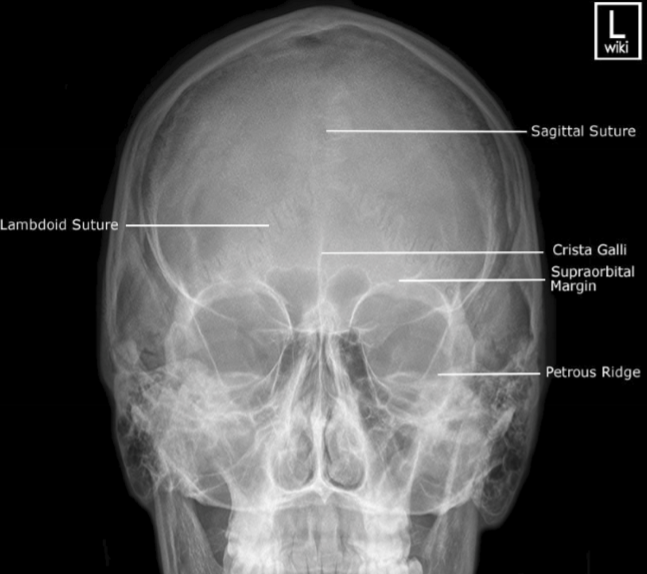

Please label